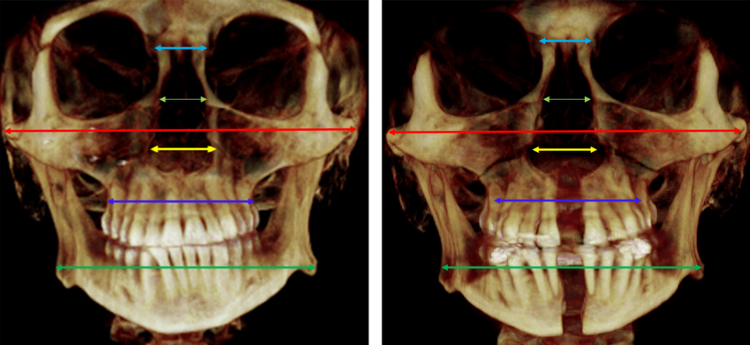

Кстати сами смотрите свои снимки перед брекетами и, если мало кости, то это хуёвая затея - можно без зубов остаться в итоге.